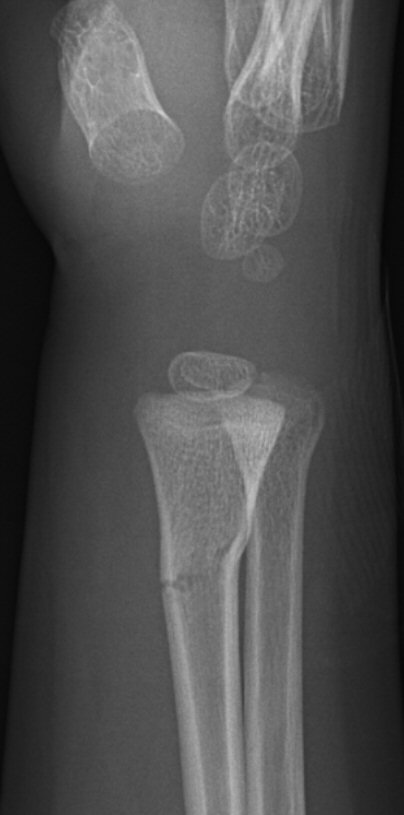

Dorsalbockad distal radiusfyseolys Salter-Harris typ 2 före och efter reposition